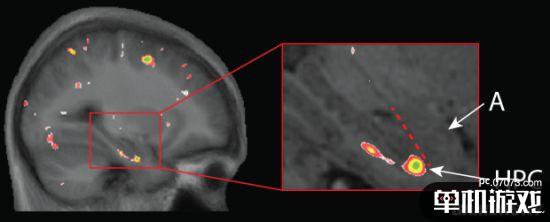

以下是18-30岁此前不玩FPS游戏的健康男女体验相关游戏90小时后,大脑中海马体的变化情况。

脑部扫描显示大脑灰质丢失